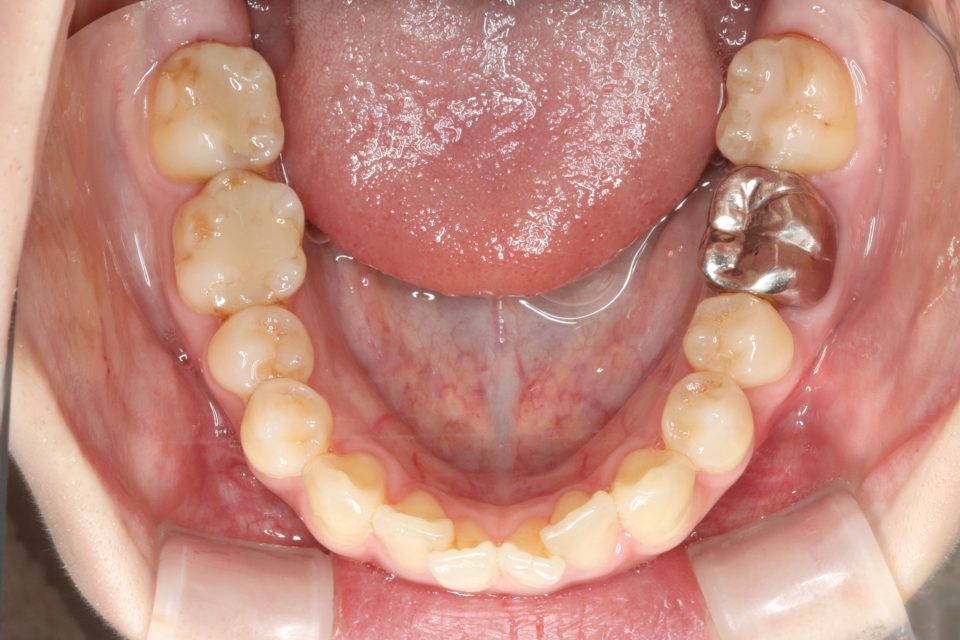

矯正治療前

きれいに並びきるよう歯のやすりがけ(IPR)をしています。

歯を動かす治療は終了し、

現在は上下の前歯の裏側に後戻り防止の針金(FIX)を貼り、

定期的なチェックをしています。